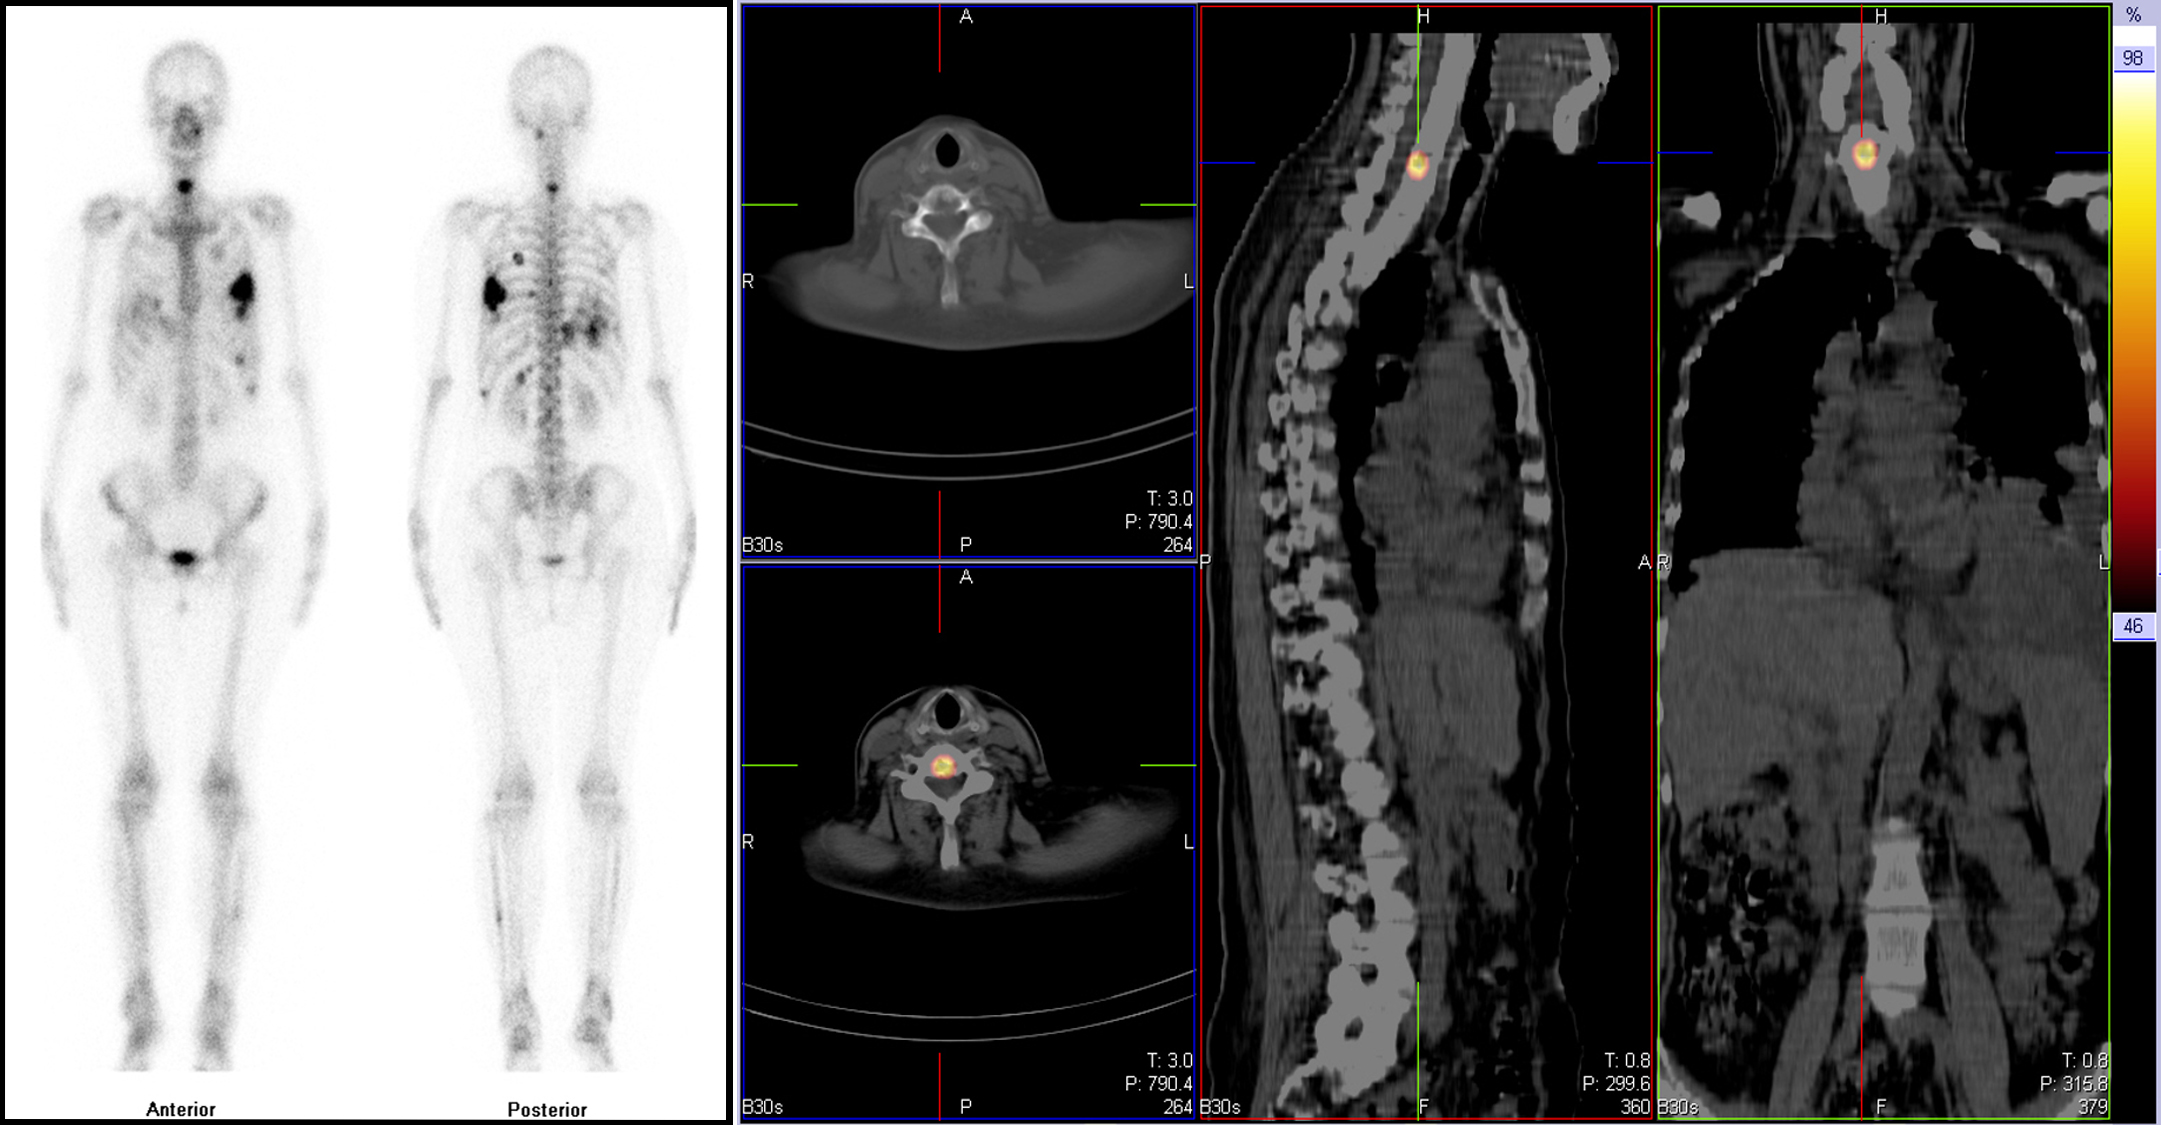

全身骨显像(左)结合体部SPECT/CT断层显像融合(右)显示颈6椎体骨质破坏